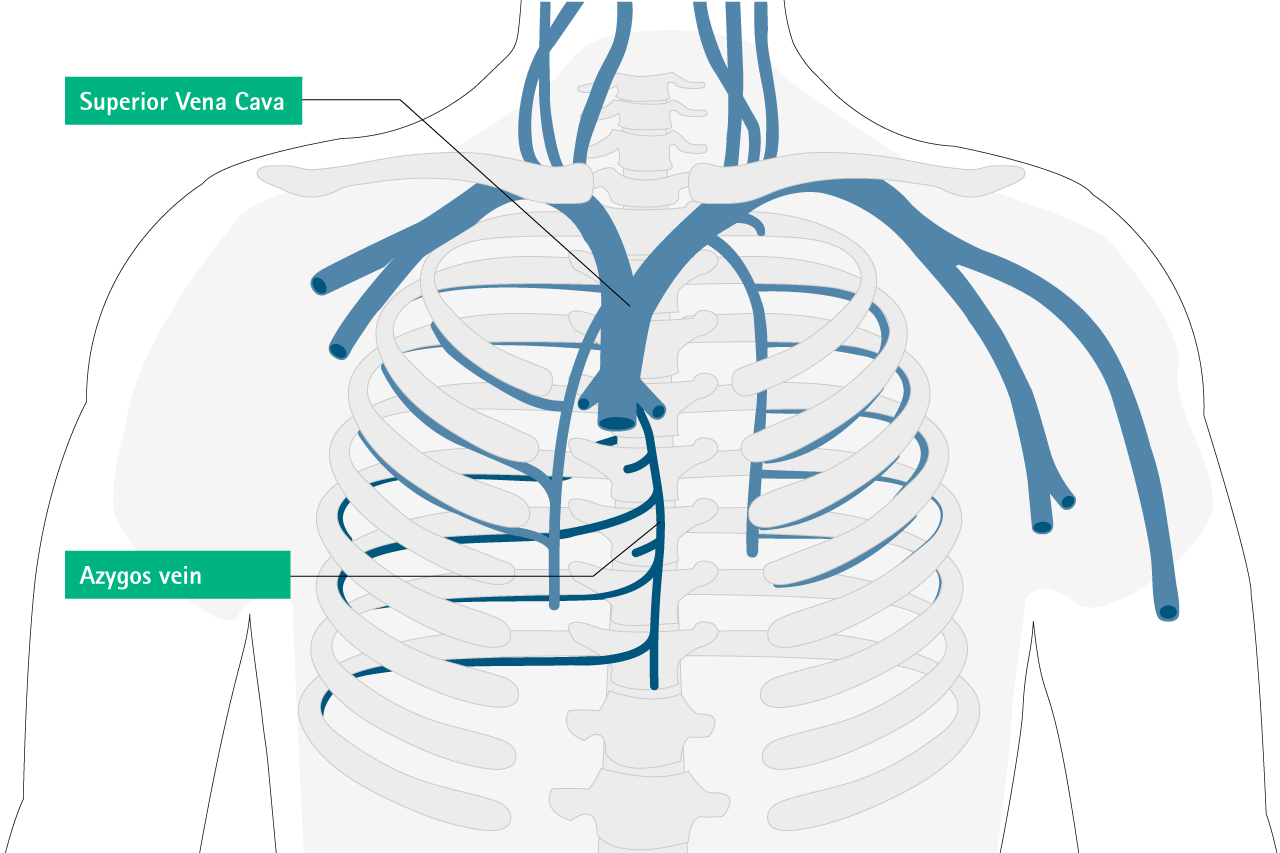

scheme of catheter tip position Caers J, Fontaine C,Vinh-Hung V et al (2005) Catheter tip position as a risk factor for thrombosis associated with the use of subcutaneous infusion ports. Support Care Cancer 13:325-331​

Azygos veinPericardium

Azygos vein; pleural diffusion pulmonary edema, dyspnea, chest pain, back pack pain